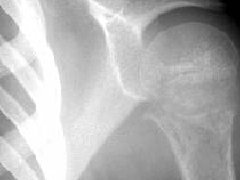

骨软骨瘤-恶变